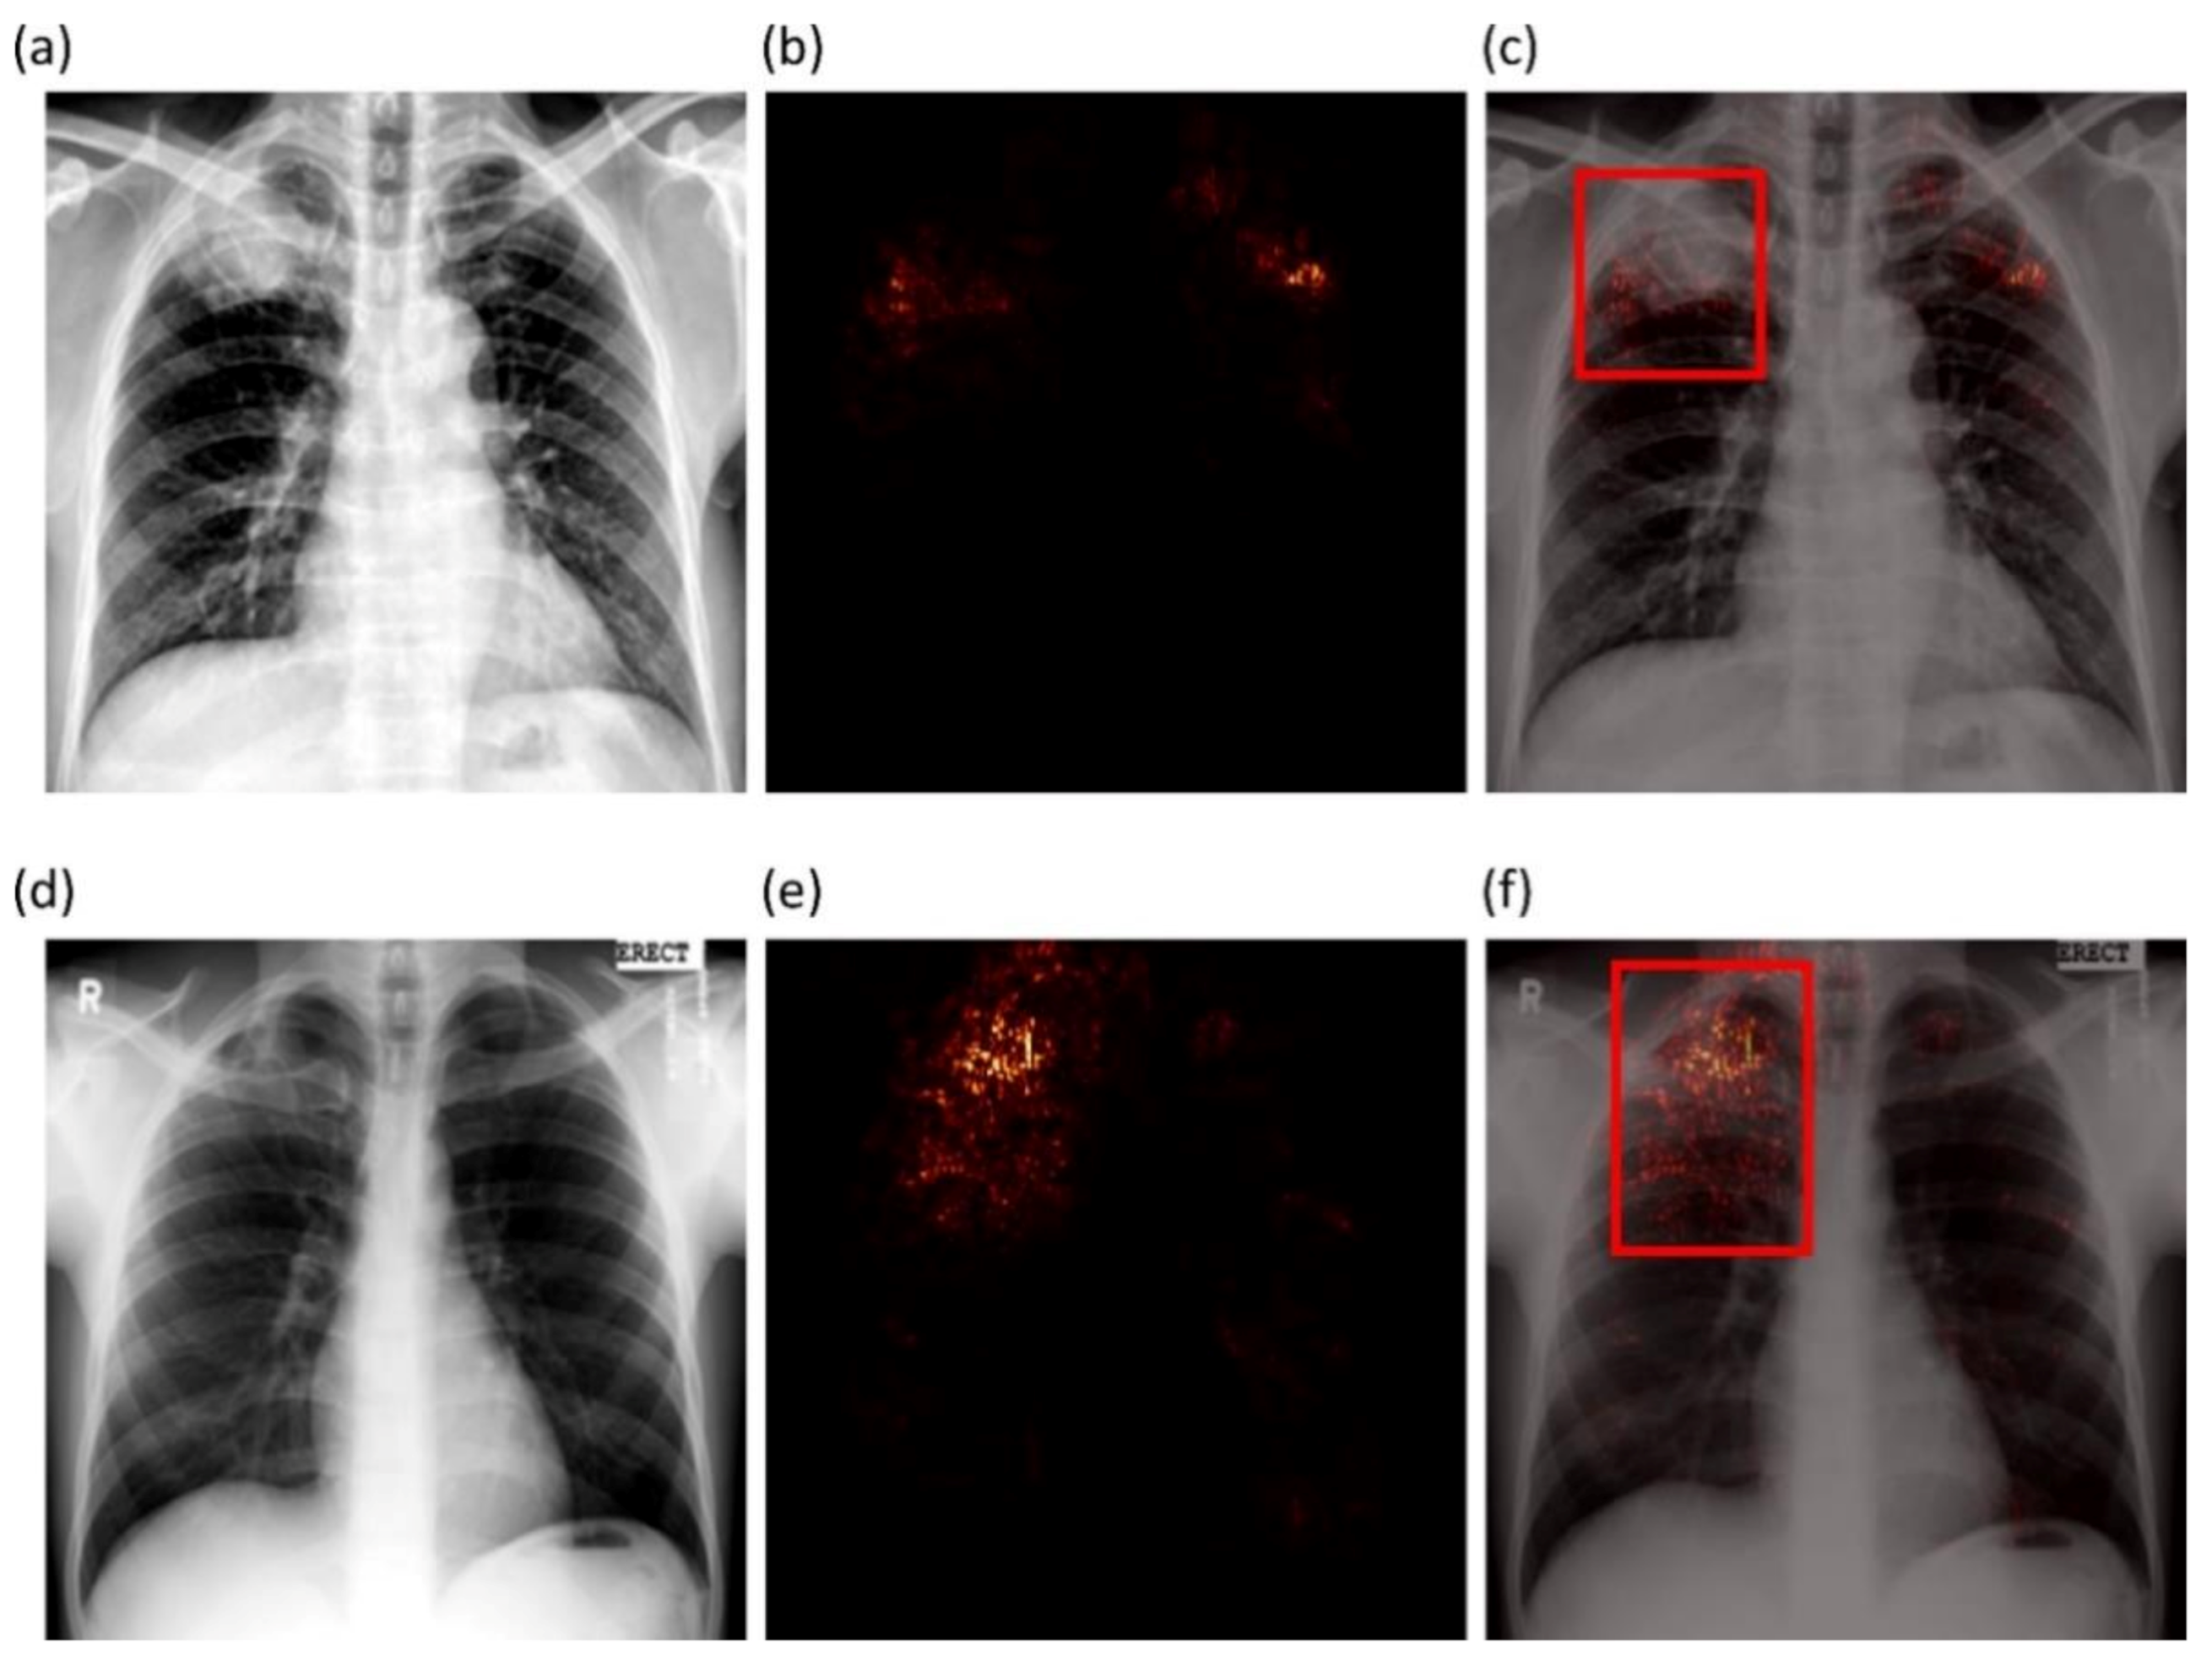

2.6. Verifying ROI Localization

We used saliency maps and a CRM-based localization algorithm [

34] to interpret the learned behavior of the fine-tuned models toward detecting TB manifestations. These algorithms provide a visual interpretation of model predictions and supplement clinical decision-making. The algorithms differ by the methods in backpropagating the derivatives and the use of feature maps. Saliency maps measure the derivative of the output category score concerning the original input and generate a heat-map with the original input image resolution. A higher derivative value signifies the importance of that activation in contributing to the final category score. A smaller value for the derivative results in negligible impact, and the activation can thus be considered trivial toward final prediction.

CRM-based visualization algorithms are demonstrated to deliver superior localization performance as compared to the conventional class-activation map (CAM)-based localization, particularly toward medical image analysis [

34]. Unlike CAM-based visualization, CRM-based localization underscores the fact that the feature maps contribute to decreasing the prediction scores for other class categories in addition to increasing the scores for the expected category. Such discrimination helps in maximizing the difference between these scores and results in superior discrimination of class-specific ROI by measuring the incremental mean-squared error from the output nodes. The features are extracted from the deepest convolutional layer of the best-performing fine-tuned model. The CRM algorithm is used to localize the ROI involved in classifying the CXRs as showing pulmonary TB manifestations. The feature map dimensions vary across the models. Hence, the CRMs are upscaled through normalization methods to match the spatial resolution of the input image. The computed CRMs are overlaid on the original image to localize the TB-consistent ROI that is used to categorize the CXRs as showing pulmonary TB manifestations. The CRMs are generated for the CXRs with TB-category labels toward visualizing the regions of TB manifestations. We further converted these CRM-based weak TB-consistent ROI localizations to binary ROI masks. The original CXRs and the associated ROI masks are used for further analysis.

Verifying ROI localization: neural networks make use of inherent learning methods to identify salient features in the input data. However, data-driven DL models are considered back-boxes since they lack explainability. Therefore, it is crucial to determine if these models are predicting the expected classes for the right reasons. Saliency maps and other visual ablation studies help to investigate if the models learn salient feature representations conforming to the experts’ knowledge of the problem. In this study, we used saliency maps and CRM-based localization algorithms to illustrate and explain the localization behavior of the trained models. We observed that the TB-consistent ROI localization obtained with the CXR modality-specific fine-tuned models are superior to those obtained using the ImageNet-pretrained models. Such superior localization performance could be attributed to the following characteristics: (i) the fine-tuned models inherit CXR modality-specific knowledge compared to that transferred from the natural image domain; (ii) the transferred knowledge is relevant to the target modality; (iii) the fine-tuned models are empirically truncated at the optimal depth to learn relevant and salient feature representations. This helped to deliver superior classification and localization performance. These observations are reinforced by the suboptimal localization performance observed with the out-of-the-box ImageNet-pretrained models.